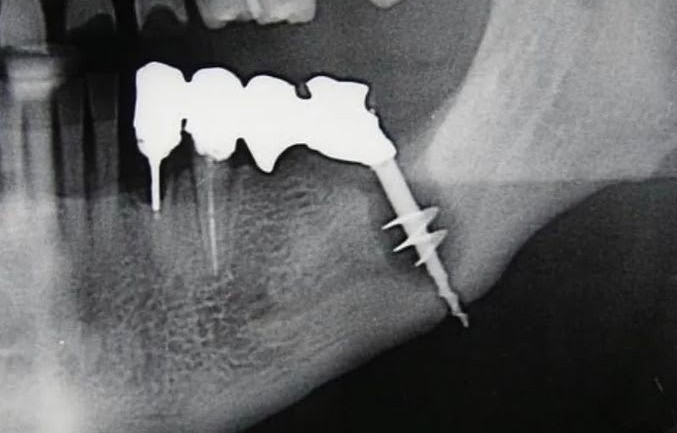

Teaching MINIMALLY INVASIVE surgery from a periodontist with videos that cover: Extractions (simple & complex), simple Dental Implant placements, Extractions & Immediate placements, and advanced surgical procedures (gummy smile surgeries, advanced bone grafting).